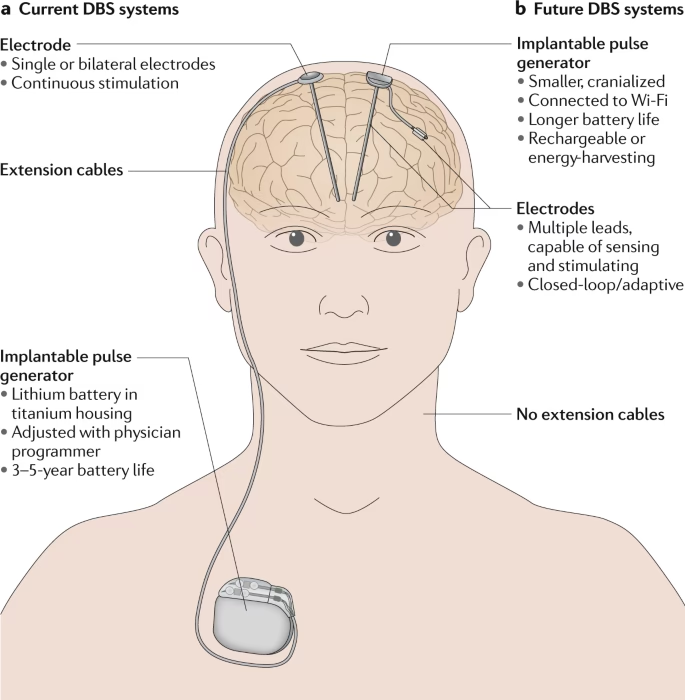

La ECP implica la implantación de electrodos finos en áreas específicas del cerebro que controlan el movimiento o el estado de ánimo. Estos electrodos están conectados a un dispositivo similar a un marcapasos, llamado neuroestimulador, que se implanta debajo de la piel, generalmente cerca de la clavícula. Este dispositivo envía pulsos eléctricos continuos a las regiones cerebrales objetivo, ayudando a modular la actividad neuronal desorganizada que causa los síntomas.

El proceso comienza con la determinación precisa de la ubicación óptima para la colocación de los electrodos (llamados 'leads'). Neurocirujanos experimentados implantan uno o más de estos leads dentro de estructuras cerebrales específicas. Estos leads se conectan a través de un cable aislado de extensión a un pequeño neuroestimulador que, como se mencionó, se coloca quirúrgicamente bajo la piel, usualmente en la parte superior del pecho.

Una vez que el neuroestimulador está en su lugar y se ha completado la recuperación inicial de la cirugía, el médico procede a programar el dispositivo. Este paso es crucial y a menudo requiere múltiples visitas a lo largo de varias semanas o meses. Durante estas sesiones de programación, el médico ajusta los parámetros de la estimulación eléctrica (como la frecuencia, la amplitud y la anchura del pulso) para encontrar el equilibrio ideal entre el control de los síntomas y la minimización de los posibles efectos secundarios. Es un arte y una ciencia que se adapta a la respuesta individual de cada paciente.

La implantación del neuroestimulador se realiza generalmente bajo anestesia general. Se crea un 'bolsillo' bajo la piel, usualmente debajo de la clavícula o en el pecho/abdomen, y se coloca el dispositivo. El cable de extensión del lead cerebral se conecta al neuroestimulador. Las incisiones se cierran con suturas o adhesivos.

El neuroestimulador funciona con una batería que necesita ser reemplazada periódicamente (generalmente cada 3 a 5 años, aunque los modelos recargables duran más). El reemplazo de la batería es un procedimiento ambulatorio menos invasivo que la cirugía inicial.